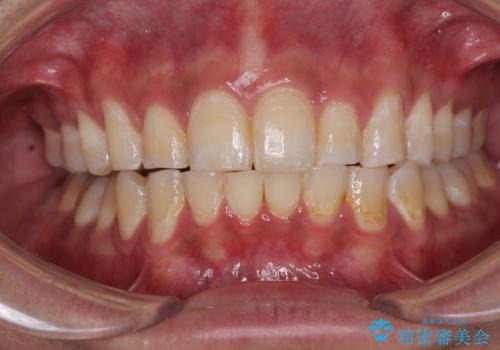

深い咬み合わせと前歯のデコボコ ワイヤー装置での抜歯矯正

【モニター】デコボコ前歯を治したい ワイヤー装置での抜歯矯正治療